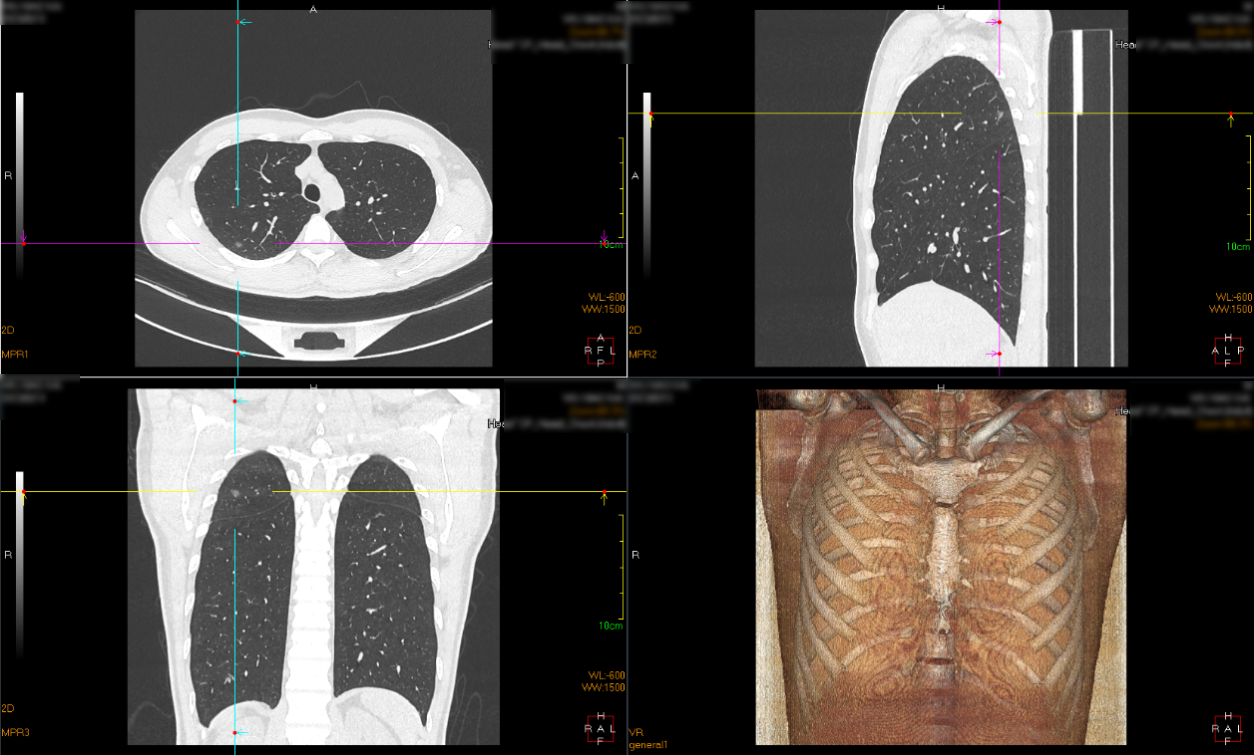

定位前扫描三维

定位后扫描三维

定位针与病灶位置

再次扫描,评估定位情况;摆放体位,消毒,开始手术;右上肺后段切除后,切开病灶,可见病灶与定位点毗邻,术中快速病理示右上肺结节为微浸润腺癌,手术顺利,患者安然返回病房。